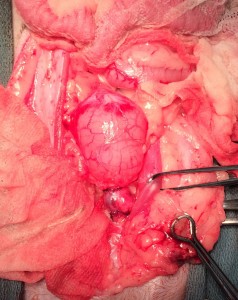

子宮蓄膿症

子宮内に膿みが貯まり大きくなっています